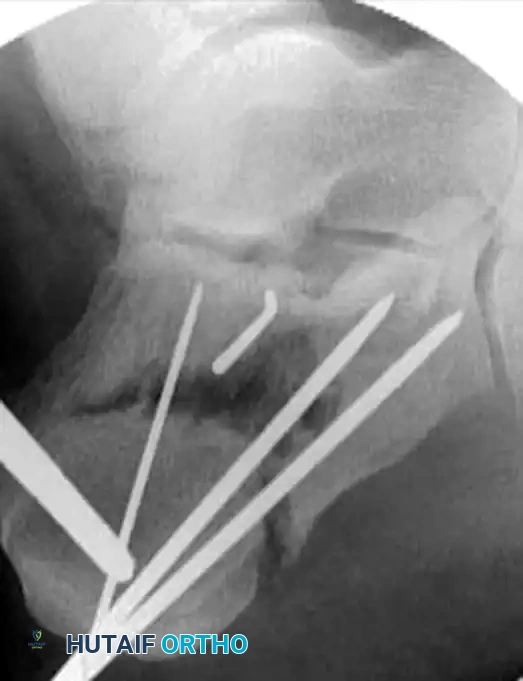

Definitive stabilization is achieved using cannulated screws, which provide compression across the fracture lines and rigid maintenance of the restored anatomy.

- Place 3.5-mm or 4.0-mm partially threaded cortical screws over the provisional K-wires. These screws are directed from lateral to medial, compressing the lateral articular fragment against the medial sustentacular fragment.

- To maintain the corrected position of the tuberosity, insert fully threaded screws from the posterior tuberosity directed anteriorly toward the calcaneocuboid joint, parallel to the initial Steinmann pin. Fully threaded screws are preferred here to act as position screws, preventing loss of calcaneal length.

- Remove the Steinmann pin and any remaining provisional K-wires.

- Perform a final fluoroscopic check to confirm extra-articular hardware placement, restoration of Böhler’s angle, and correction of varus alignment.